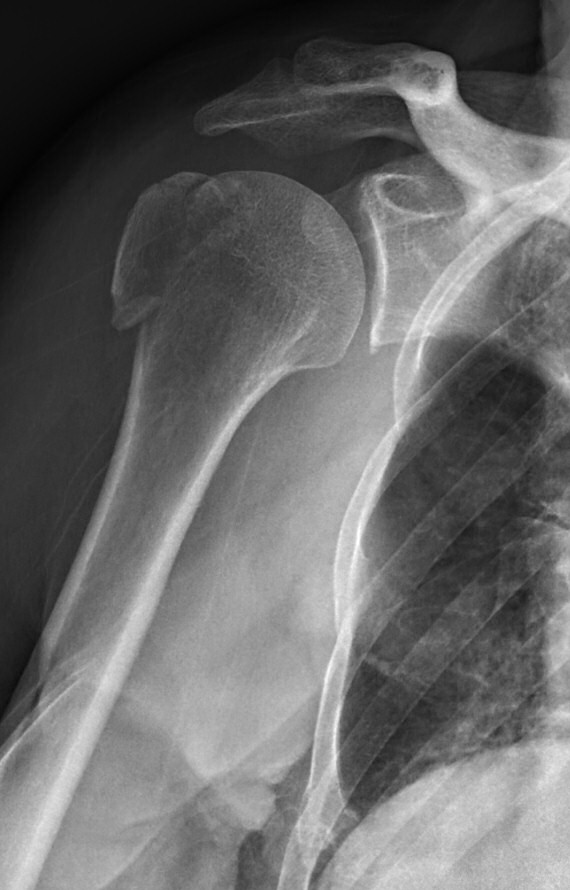

Axelluxation med avlöst tuberkulum majus innan och efter reponering i narkos. Efter reponering förbättrat läge men även misstänkt bony bankart-skada med litet fragment inferiort om glenoiden.